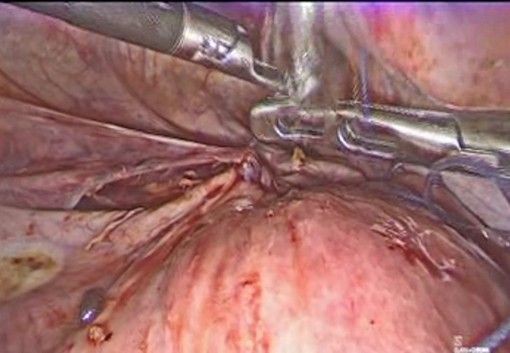

A 36-year-old female patient, G2 P1 A1, with no significant medical history. Her first pregnancy ended with a cesarean section at 27 weeks due to cervical incompetence, with a newborn weighing 850 g. She subsequently suffered an incomplete miscarriage at 19 weeks, also secondary to cervical incompetence, resolved by instrumental uterine curettage. Given the clear history of cervical incompetence, a laparoscopic transabdominal Benson-Durfee cerclage was performed. The procedure was performed without complications, the procedure lasted 60 minutes, a V Care type uterine mobilizer was used, with an estimated blood loss of 100 ml, and she was discharged the following day. Subsequently, the patient continued with follow-up and ultrasound confirmed the correct placement of the cerclage. (Figure 1).

Figure 1: Green arrow: correct placement of the cerclage